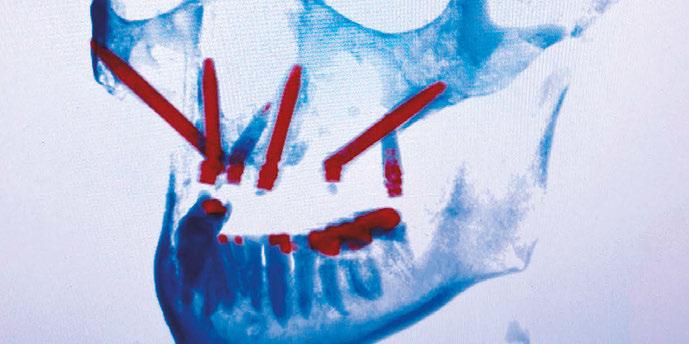

Treatment of severely atrophic maxillae often requires highly advanced procedures such as quad-zygomatic implants1-3 (Figure 1) or customized subperiosteal implants (Figure 2).4,5 Quad-zygomatic implant treatment has a long history of success, but requires significant surgical expertise due to limited malar bone availability and propinquity to anatomic structures such as the orbit and infraorbital nerve.6 Customized subperiosteal implants, on the other hand, are a promising new treatment option but have limited long-term follow-up data and significant expense.7 Transnasal dental implants have recently been introduced as another option for treatment of severely atrophic maxillae, specifically as an alternative to quad-zygomatic implant placement (Figure 3).8 Transnasal implants may serve as a replacement for anterosuperior zygomatic implants as they tangentially traverse the interior lateral nasal wall and achieve high insertion torque via 3 mm-5 mm of apical engagement in the confluence of the inferior concha, lateral nasal wall, and frontal process of the maxilla (Figure 4).8-16

Figure 1 (left): 3-dimensional CBCT rendering of patient treated with quad-zygomatic implants. Figure 2 (right): Example of customized subperiosteal dental implant for treatment of an atrophic maxilla